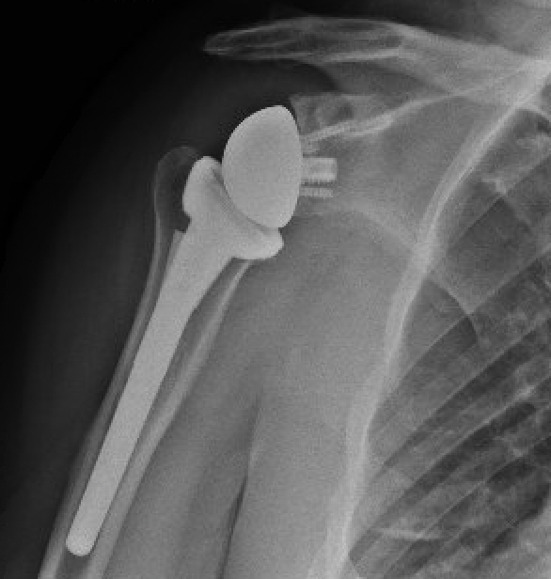

With the glenoid completed, attention was returned to the humeral head preparation. After identifying optimal implant sizing, the trial components were removed, and the canal was lavaged with double antibiotic pulse lavage. The SurgiphorTM and SurgiRinseTM steps were again repeated, and vancomycin powder was then placed down the humeral canal prior to final implant placement. It should be noted that surgical gloves were changed by the entire sterile field team prior to implant placement throughout the case. A final range of motion and stability check was performed, and the deep wound was irrigated with the pulse lavage. Prior to closure of the deltopectoral interval, hemostatic powder was placed into the deep wound and a second dose of one gram of TXA was given (Picture 4). After deltopectoral closure, the superficial wound was irrigated again using the SurgiphorTM and SurgiRinseTM combination. The remaining hemostatic powder was then placed in the subcutaneous fat layer to decrease postoperative seroma and adhesion formation. The wound was closed in a layered manner and a running Monocryl suture on the skin, followed by a watertight sealant glue. The patient was discharged to home on a 10-day course of oral doxycycline, 100mg BID. Radiographs were taken at the first postoperative visit two weeks after the procedure (Picture 5).